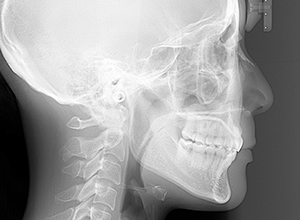

初診時

FP・IOP

X-Ray

X-Ray所見

セファロ所見 Or-R平面からRは上方に位置づいている。中顔面部の奥行きはあるもののNasionからA点までは距離があるため、下顎は後下方へ回転している。